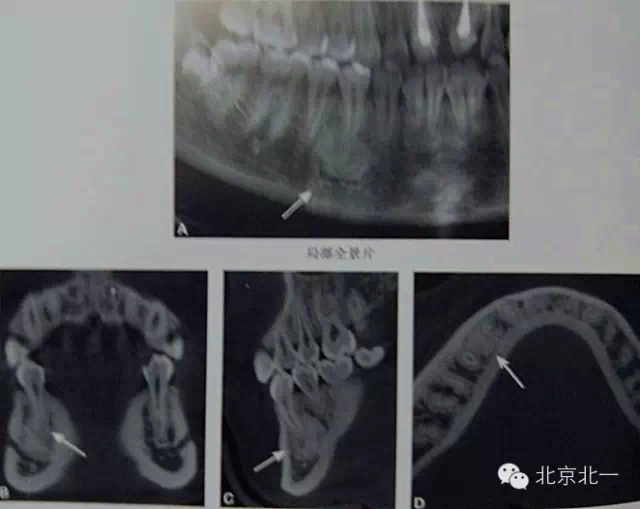

3)骨島:

概述:

主要和根尖型骨島鑒別,主要集中位于根尖區(qū)的骨島,

【CBCT表現(xiàn)】:

在CBCT上,根尖型骨島無低密度帶狀影包繞,與周圍骨質(zhì)分界清晰,具有特征性的毛刷樣邊緣,且其發(fā)生區(qū)域的牙根牙周膜影像連續(xù)、完整、不導致頜骨的膨隆。

右下頜C4根尖區(qū)課件一類圓形高密度影,與周圍骨質(zhì)分界清晰,C4牙周膜影像連續(xù)、完整,下頜骨未見膨隆。